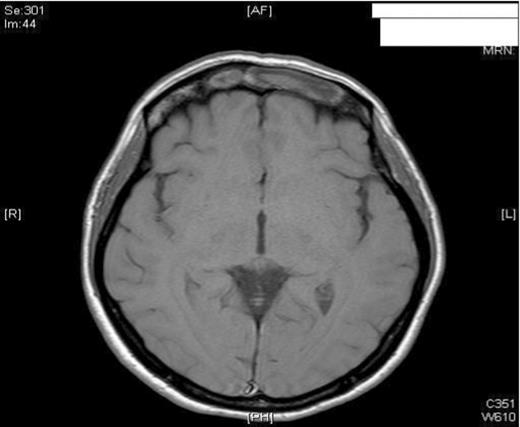

The patient had an uneventful post-operative period and remained pain-free with no residual swelling of the forehead. She was discharged home 24 hours post-operatively with FlixonaseTM Nasules for 6 weeks, SterimarTM spray for 2 months and regular steam inhalations. At 6 months post-op, the patient remained asymptomatic and well. To avoid any unnecessary radiation, the patient was assessed with MRI imaging. As shown, the imaging revealed no complications and showed adequate resolution of the mucocele (Figure 3).

MRI imaging (a) coronal (b) axial views post procedure revealing resolution of the mucocele and no intracranial or orbital complications (see figure 1).